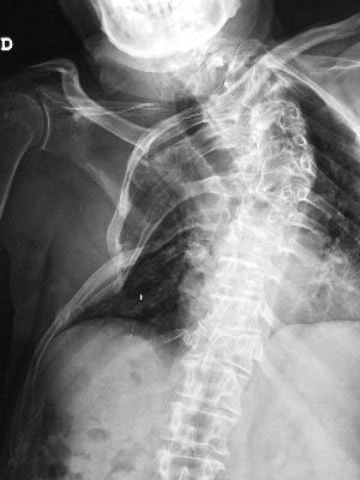

MO Fractura de omóplato y de costillas 2 a 8 derechas. Accidente de tráfico con moto en paciente centenaria. 1

MO Fractura de omóplato y de costillas 2 a 8 derechas. Accidente de tráfico con moto en paciente centenaria.2